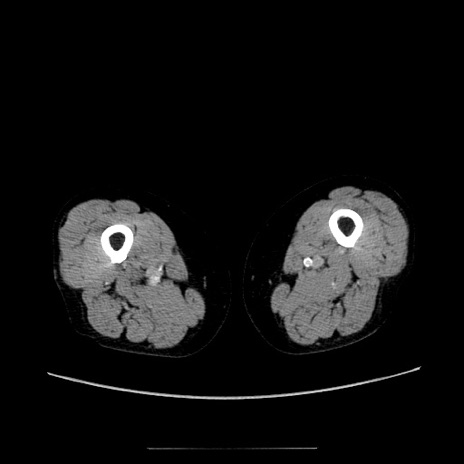

症例5(横断像)

【症例】70歳代女性

【主訴】お腹が張る

【現病歴】1週間くらい前から腹部膨満の自覚あり。昨日夜から増悪したため、本日救急外来受診。

【身体所見】意識清明、BT 36.5℃、BP 165/106mmHg、HR 80bpm、SpO2 98%、腹部:膨満、軟、自発痛・圧痛なし、触診にて不快感あり、腸蠕動音:減弱

【データ】WBC 12600、CRP 1.04